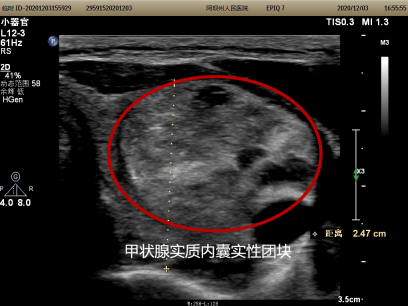

“感谢外二科的医生们给我做这个手术,脖子上一点疤都没有留。”40岁的李女士,因彩超发现左侧颈部包块4天于2020年12月7日入住州人民医院外二科,入院后经全面检查诊断为甲状腺左叶腺瘤(大小为22×2.6×3.7cm),传统开放的甲状腺包块摘除术无论是做横弧型切口还是“L”型切口都会留下非常长的疤痕,尤其是横弧型切口乍一看像是“自杀线”,很多女性患者,尤其是年轻女性患者会难以接受,李女士非常担心手术后会在脖子上留一道很长的疤痕并对手术很畏惧。术前,外二科的医师们大讨论为患者制定了详细的手术和治疗计划并给患者进行了详细的讲解,取得了患者的信任。